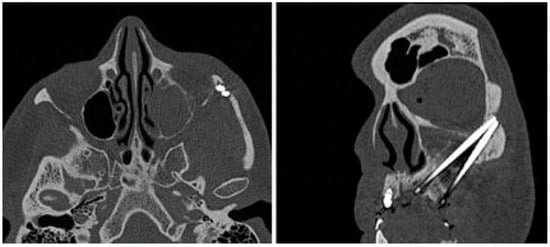

Figure 4.

CT axial and coronal view: two ZIs on the left zygoma with apex in contact without adequate inter-implant distance and outer cortical bone resorption.

The implant apex was not palpable under the skin of the zygomatic bone. The patient was operated on under general anaesthesia with intraoral and external approach. The cutaneous fistula was excised and after removing the granulation tissue, 1 cm diameter bone resorption was noted (Figure 5), confirming the CT reports (Figure 4). The Zis apex was in contact, without inter-implant distance (Figure 4).